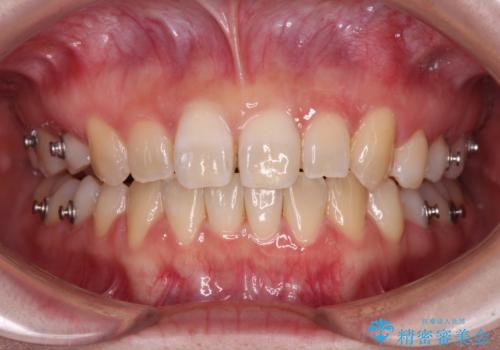

ディープバイトをインビザライン矯正で改善

- 前歯のデコボコと強い咬みしめを気にして来院された患者様です。

インビザラインを用いて、前歯の叢生を解消するとともに、ディープバイトを改善していくこととしました。

上顎に乳歯が左右1本ずつ残っていたため、若干咬み合わせに不具合が残りましたが、強い咬合力の原因であったディープバイトをしっかりと改善することができました。